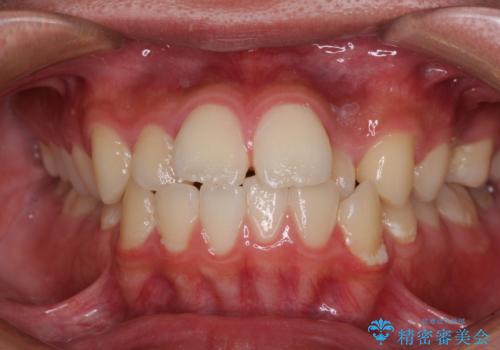

矯正歯科治療 → 上下顎前突(口ゴボ)

- デコボコと口元の突出感を改善 抜歯矯正治療